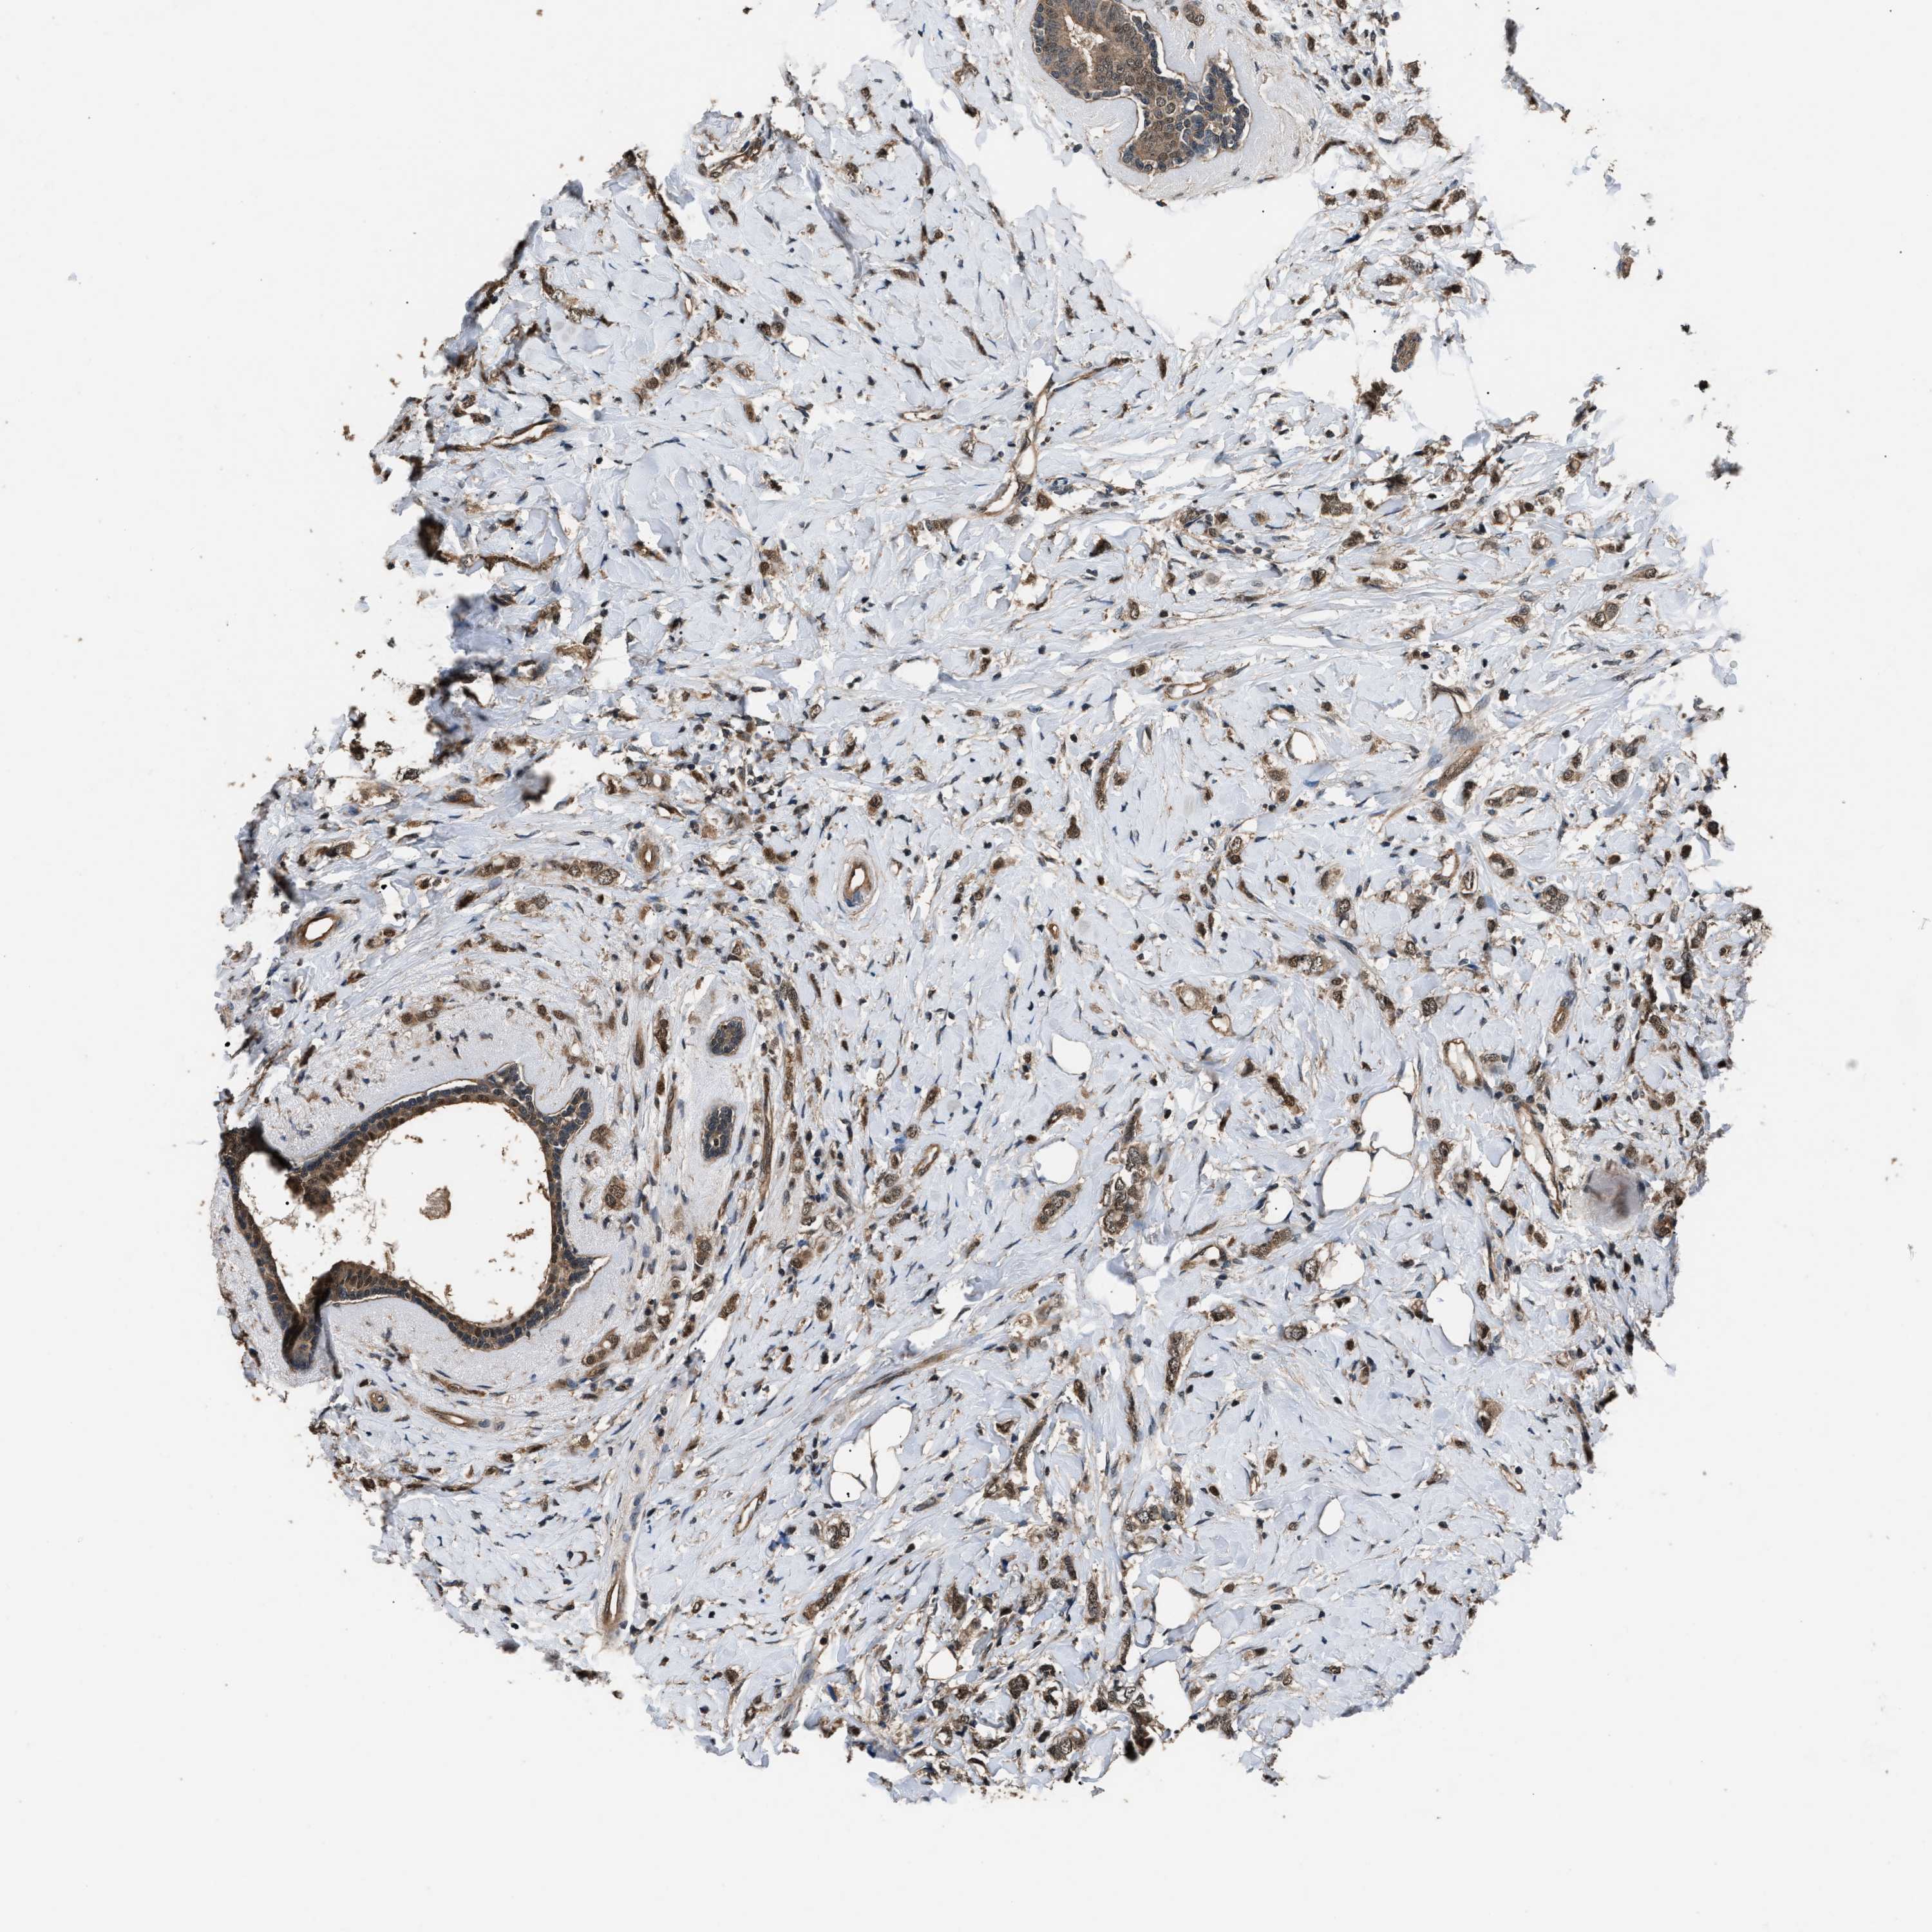

CANCER BREAST CANCER Show tissue menu

BRCA TCGA BRCA VALIDATION PROTEIN EXPRESSION